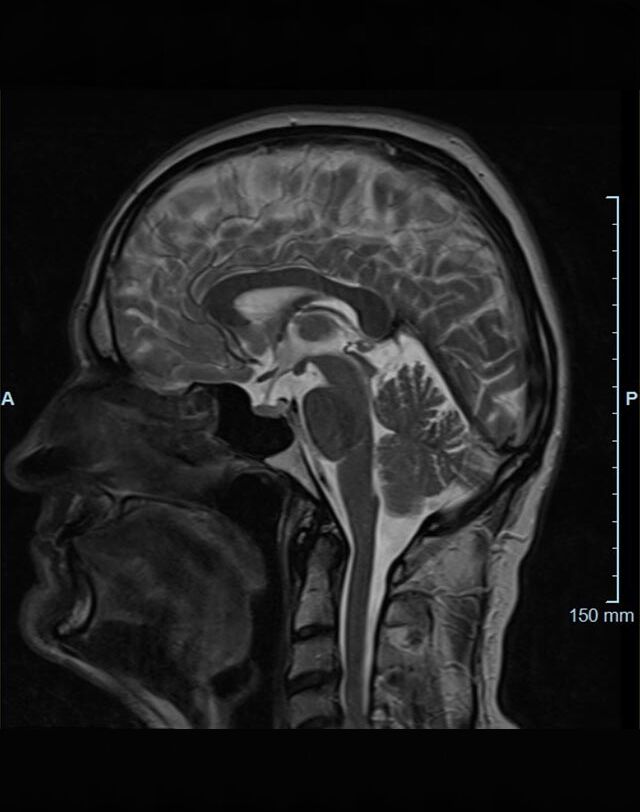

Kopf/Hals

• akute Schlaganfalldiagnostik und chronische Durchblutungsstörungen

• entzündliche Prozesse des Gehirns oder der Gesichtsweichteile

• Tumore

• Abklärung Schwindel, zentrale Sehstörung, Kopfschmerz

• Metastasenverdacht

• Multiple Sklerose

• Abklärung Hirnnerven, Schädelbasis inkl. Hypophyse

• Abklärung Kleinhirn, Hirnstamm, Halsmark

• intrakranielle Gefäße (Abklärung Verschluss, Stenose, Aneurysma)

• Halsgefäße zur Therapieplanung (z.B. Stent, Operation)